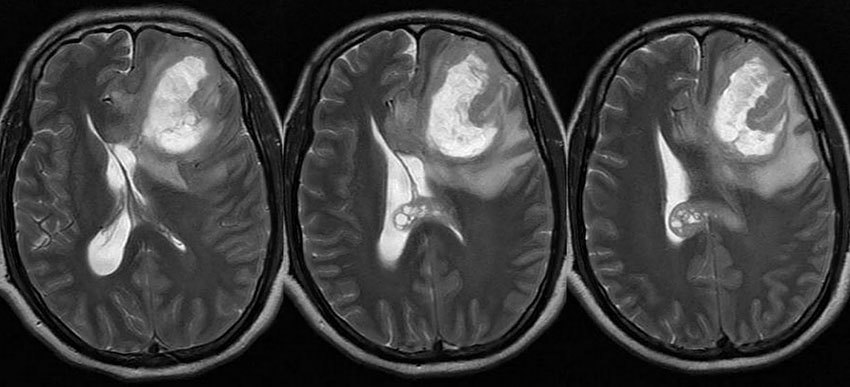

Ранняя диагностика рака головного мозга теоретически возможна, но маловероятна. Скрининг (профилактическое обследование клинически здоровых лиц) проводят лишь пациентам из групп риска, имеющим отягощенную наследственность или генетические синдромы. Новообразование может быть выявлено при помощи КТ или МРТ мозга.

Большинство пациентов обращаются к врачу уже после появления первых симптомов рака мозга. Основным методом диагностики является МРТ. Именно эта методика позволяет получить детальное изображение всех структур мозга, выявить опухоли даже небольшого размера, предположить их гистологический тип ещё до проведения гистологического исследования.